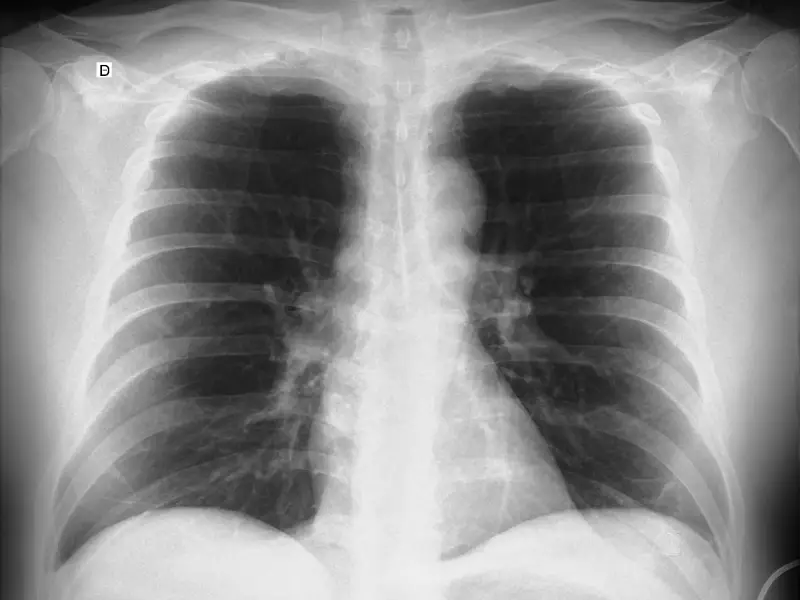

Densidad agua en radiografía de tórax

Densidad agua en radiografía de tórax Presentación Edad: Género: Discusión Artículos